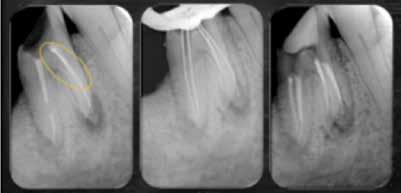

A betört műszerek eltávolításának művészete

Dr. Juan Carlos Ortiz Hugues

Kudarcként éljük meg, amikor egy gyökérkezelő eszköz a kezelés közben betörik a gyökércsatornába. Azonban megfelelő tapasztalattal, egy jó stratégiával és modern eszközök segítségével ez a rettegett szövődmény is klinikai sikerré alakítható.

A cikk megírásával az volt a célom, hogy bemutassam a gyökérkezelés során bekövetkező endodonciai műszertörések kockázati tényezőit, okait, megelőzési stratégiáit, valamint a törött eszközök eltávolításához alkalmazott klinikai protokollokat, segédeszközöket, beleértve az ultrahangos, tubusos és huroktechnikákat. Kitérek a nagyítás, a csatorna anatómiájának és az irrigálás szerepére is.

3a 3b

3. a–3. d ábrák: Műszereltávolítás a mesiolingvális csatornából és újra-gyökérkezelés: a: 16×-os mikroszkópos nagyítással történt műszerlokalizáció, b: 10×-es mikroszkópos nagyítással történt műszerlokalizáció, c: K15-ös reszelővel végzett csatornafeltárás a mesiolingvális csatornában, d: A törött műszer koronális részének feltárása.

a–c ábra: Röntgenfelvételek: a: Kezelés előtti felvétel, b.: Munkahossz meghatározása, c: Gyökércsatorna-revízió utáni tömés.

Esetbemutatás

Egy 64 éves férfi jelentkezett rendelőnkbe enyhe fájdalom miatt a 19-es fogánál. A fogon egy 10 éves kerámiakorona volt, és gyökérkezelt. Az elöregedett korona a vizsgálatot megelőzően két nappal darabokra tört, így a guttapercha nyállal érintkezett. Bár a páciens tünetmentes volt, és a lágy szövetek egészségesnek tűntek, a részletes vizsgálat során rossz minőségű gyökérkezelést állapítottunk meg, valamint periapikális elváltozásokat mindkét gyökérnél. A röntgenfelvételeken az egyik mesialis gyökércsatornában egy világos, fehér sáv volt látható, amely törött műszerfragmentumra utalt (2. a–c ábrák). A mikroszkópos képek és a röntgenfelvételek elemzése után a páciens részletes tájékoztatást kapott, és teljes mértékben megértette a javasolt újra-gyökérkezelés szükségességét. A páciens értő együttműködése kulcsfontosságú. A beavatkozás alatt a mikroszkópot különböző nagyítással (alacsony, közepes és magas) alkalmaztuk. A pulpakamra falait és az alját gyémántszemcsés ultrahangos végződéssel tisztítottuk, és az egész újrakezelés alatt 5,25%-os nátrium-hipoklorit ol-

datot alkalmaztunk irrigálásra. Amikor a gyökértömés koronális harmadának guttaperchája szabaddá vált, E5-ös ultrahangos végződést használtunk a diszto-lingvális, korábban nem lokalizált csatorna feltárására, a guttapercha eltávolítására, valamint a mesiolingvális csatornában lévő törött műszerfragmentum feltárására (3–4. ábrák). Miután a kezeletlen mesiolingvális gyökércsatornában feltárult a törött műszer, az E5 ultrahangos vég aktiválása történt a fragmentum koronális része körül, teret képezve a közvetett ultrahangos rendszer számára, amelyet az ultrahangos vég aktivált.